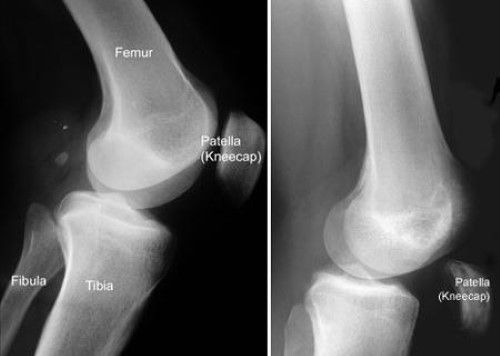

X-rays. The kneecap moves out of place and sits lower than usual when the quadriceps tendon tears. This is often very obvious on a side view X-ray of the knee. Complete tears can often be identified with these X-rays alone.

x-ray of quadriceps tendon tear

(Left) This X-ray taken from the side shows the normal location of the kneecap. (Right) The kneecap has moved out of place due to a torn quadriceps tendon. The remaining patellar tendon pulls the kneecap toward the floor.